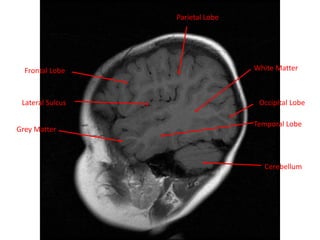

MRI BRAIN :SAGITTAL SECTIONS

White Matter

Cerebellum

Grey Matter

Frontal Lobe

Parietal Lobe

Temporal Lobe

Lateral Sulcus Occipital Lobe

Gyri of cerebral

cortex

Sulci of cerebral